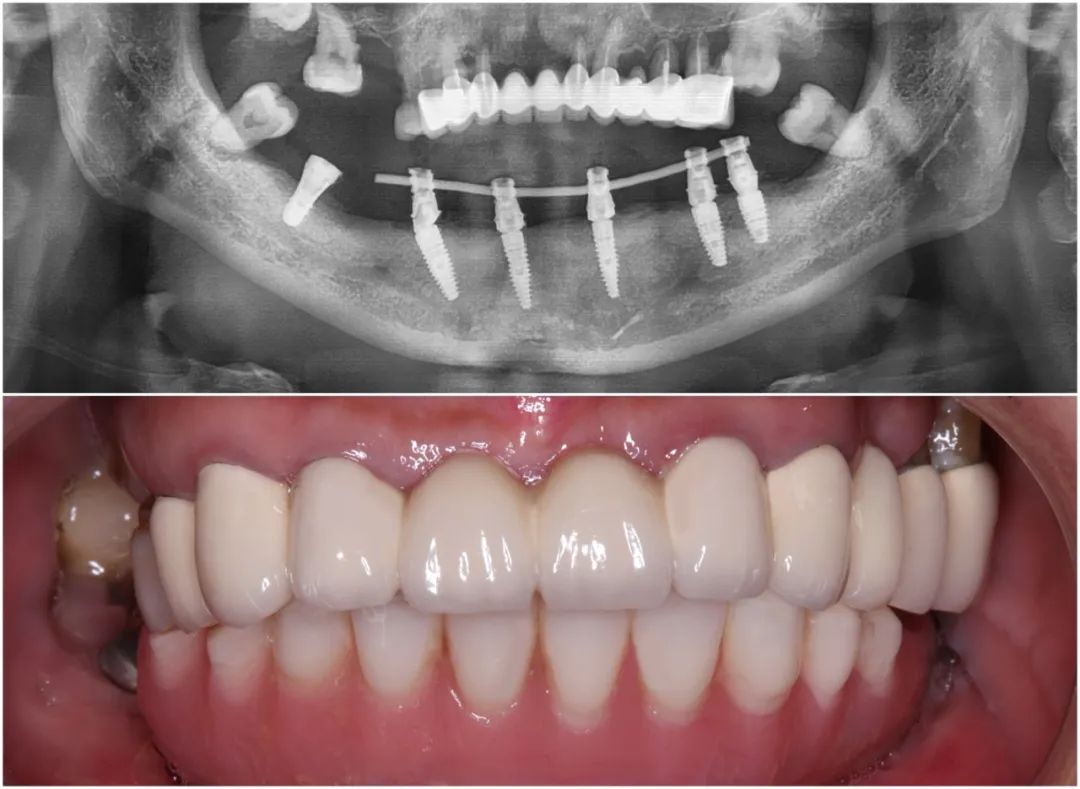

和史阿姨達成共識后,王鋒醫(yī)生先為她實施了下半口拔牙和植骨治療。經(jīng)過大半年的愈合期后,史阿姨牙槽骨量已達臨床種植條件,一次植入6顆植體并戴上臨時牙冠,即刻重拾半口好牙。

史阿姨下頜種牙后全景片及口內照